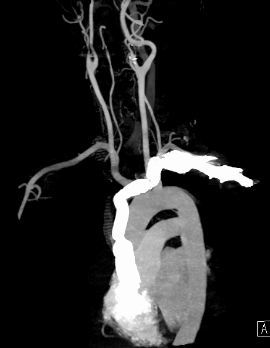

经过6个小时的通力合作,张先生的手术成功,肿块连同受侵犯的上腔静脉被完整切除,同时将左侧的无名静脉及右侧的颈内静脉与上腔静脉根部实施了人工血管搭桥。

(术中重建人工血管)

(术后MRI影像,人工血管正常运作)